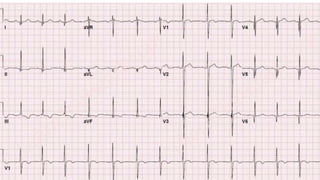

This document discusses various cases of collapse and syncope. It defines collapse as transient loss of consciousness with loss of postural tone and full recovery. Syncope is defined as loss of postural tone with or without loss of consciousness and full recovery. It then discusses the multiple potential causes of collapse and syncope including toxicological, cardiac conduction abnormalities, structural cardiac issues, autonomic dysfunction and more. It then goes through 9 case examples, discussing important questions to ask, potential tests and interventions for each case.